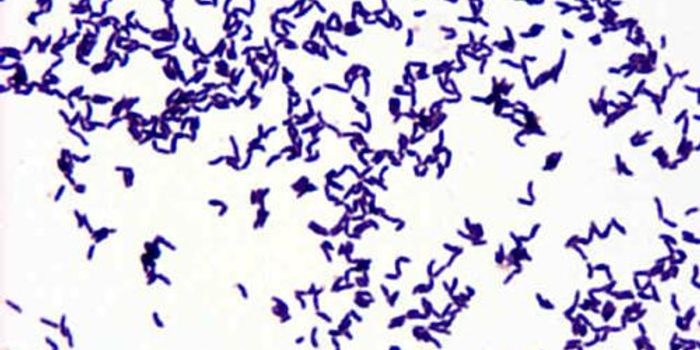

FEB 23, 2019Health & MedicineFacklamia species are Gram-positive, facultatively anaerobic bacteria that present a challenge for clinical labs to ...